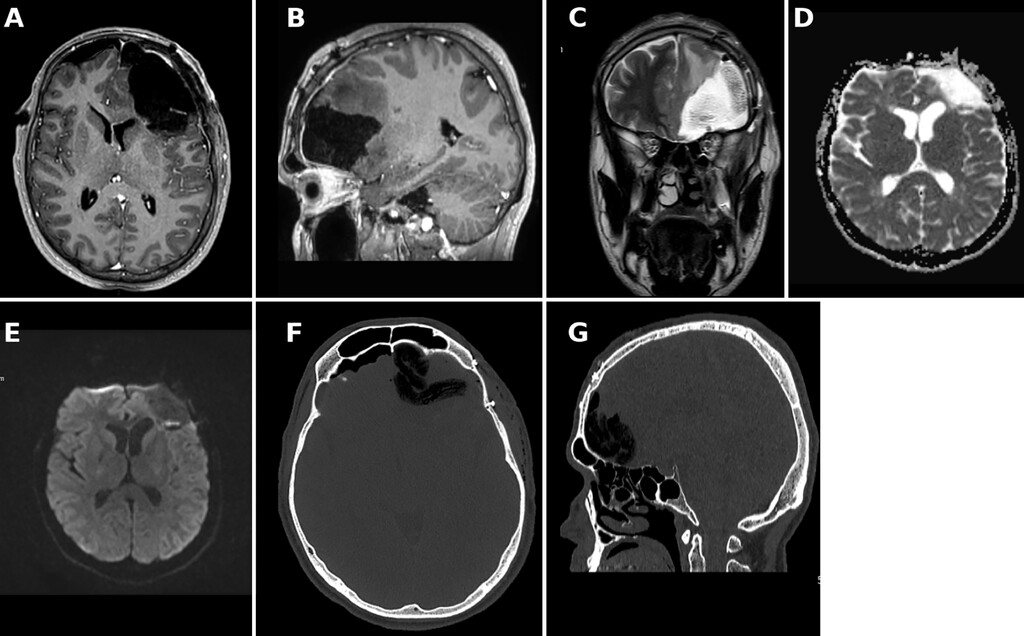

4.后续管理:术后MRI证实病灶已完整切除,无残留强化及复发积液(图4)。患者神经功能保持完好。静脉抗菌药物治疗总计6周,后续改为口服抗生素治疗3周,并持续使用抗癫痫药物。

图4:额窦相关性颅内脓肿手术引流术后多模态影像。A-C:术后MRI显示左侧额叶术后残腔,占位效应及周围水肿较前减轻。D-E:DWI及ADC图未见明显残留弥散受限。F-G:CT骨窗示额窦壁缺损及术后颅内改变。